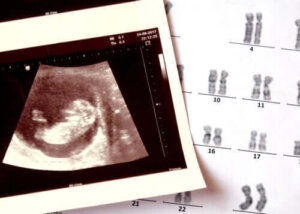

Anencefali är en medfödd sjukdom som består i frånvaron av utveckling av vissa delar av nervsystemet i barnets skalle.

Ur embryonal synvinkel utvecklas inte ett organ som kallas prosencephalon korrekt. Hos friska spädbarn är detta organ det som ger upphov till större delen av hjärnan.

Detta hälsotillstånd ingår bland de neurala rördefekterna , en grupp medfödda patologier som också inkluderar ryggmärgsbråck.

Förändringar i kromosomerna (strukturer som rymmer all information i cellerna) och vissa specifika mutationer kan bidra till dess uppkomst. Exponering för vissa miljögifter har också studerats som en möjlig determinant. Forskningsresultaten är dock inte slutgiltiga just nu.